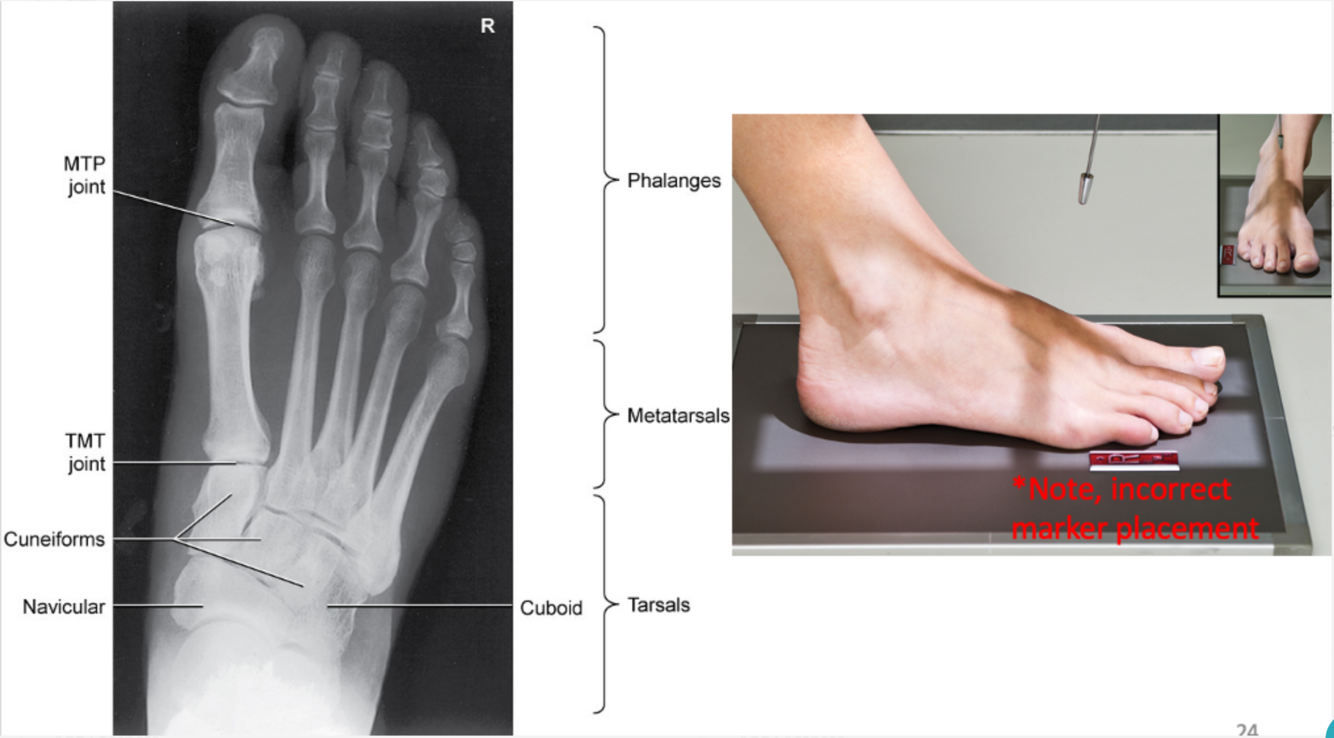

AP Axial Foot

• IR 8x10, 40 SID

• Pt seated or supine flex knee rest plantar surface on IR

• CR 10-15º angle posteriorly entering 3rd MTP

• Collimate 1” on all sides of the toes to include distal ends of metatarsals